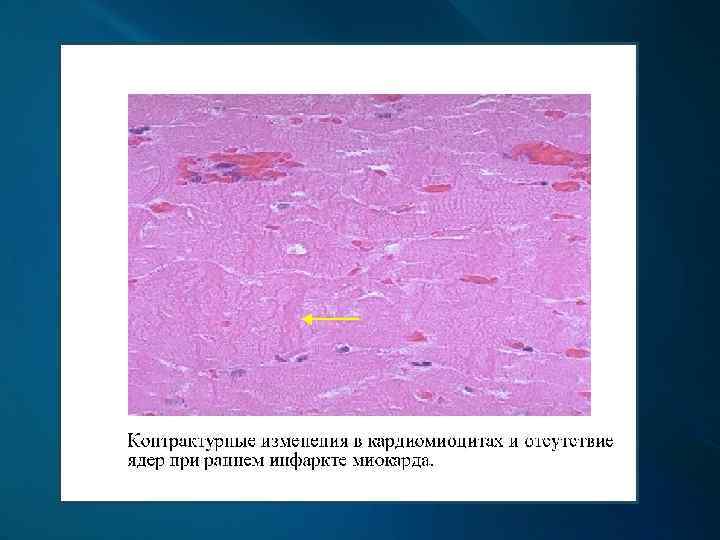

Макроскопически: первые часы - миокард дряблый, неравномерно кровенаполнен; через 18 -24 ч. – четко виден некроз; конец 1 -х сут. – некроз глинистокрасноватый, выбухает из-за отека, с геморрагическим венчиком; к 4 -6 сут. и далее – некроз западает, плотный, желто-серый, с красной каймой грануляционной ткани вокруг; через 3 -5 нед. – рубец красновато-серый, затем белесовато-серый.